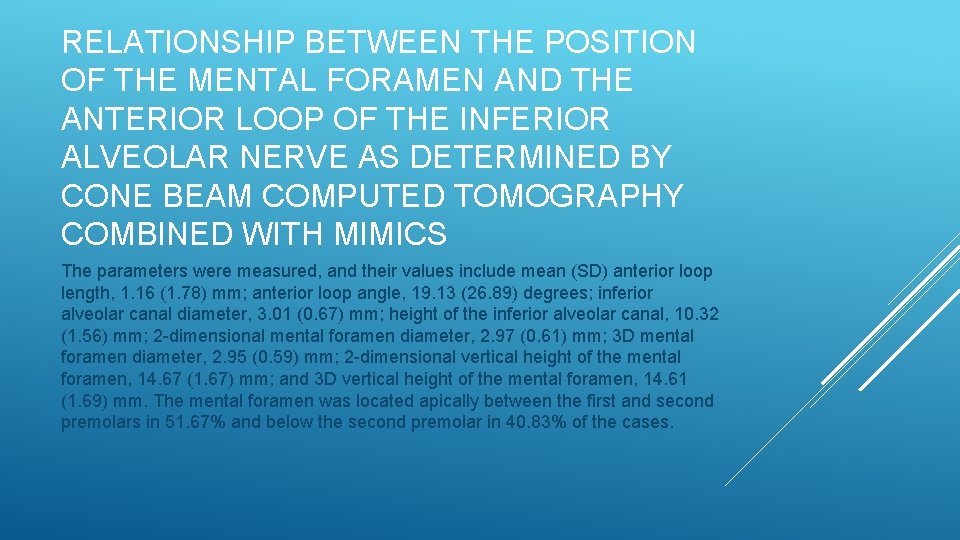

RELATIONSHIP BETWEEN THE POSITION OF THE MENTAL FORAMEN AND THE ANTERIOR LOOP OF THE INFERIOR ALVEOLAR NERVE AS DETERMINED BY CONE BEAM COMPUTED TOMOGRAPHY COMBINED WITH MIMICS The parameters were measured, and their values include mean (SD) anterior loop length, 1. 16 (1. 78) mm; anterior loop angle, 19. 13 (26. 89) degrees; inferior alveolar canal diameter, 3. 01 (0. 67) mm; height of the inferior alveolar canal, 10. 32 (1. 56) mm; 2 -dimensional mental foramen diameter, 2. 97 (0. 61) mm; 3 D mental foramen diameter, 2. 95 (0. 59) mm; 2 -dimensional vertical height of the mental foramen, 14. 67 (1. 67) mm; and 3 D vertical height of the mental foramen, 14. 61 (1. 69) mm. The mental foramen was located apically between the first and second premolars in 51. 67% and below the second premolar in 40. 83% of the cases.